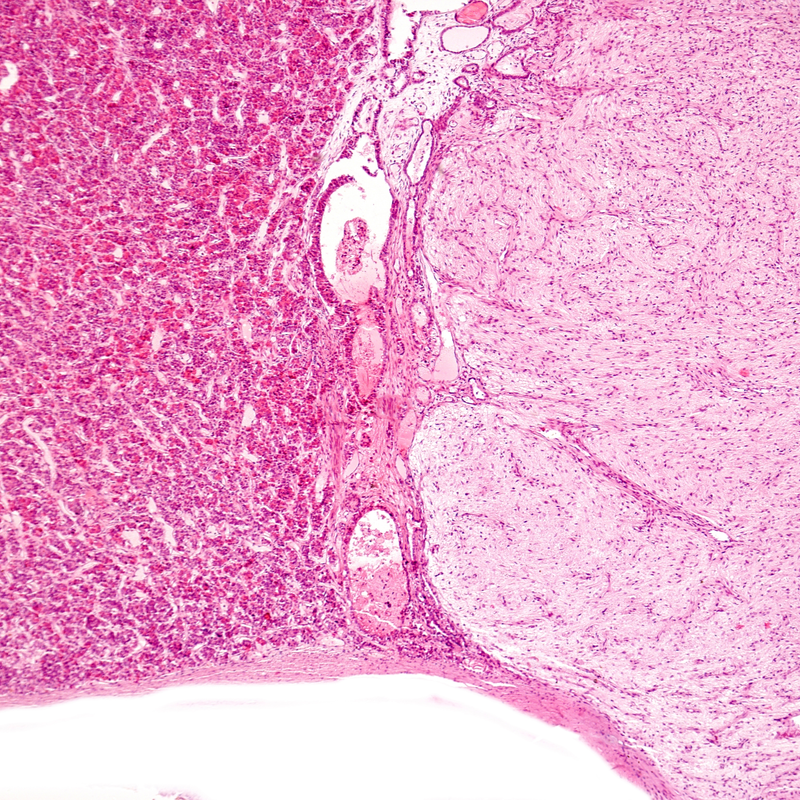

Benign tumours and frequency therapy

Being diagnosed with a benign tumour can be a frightening experience for many people.

Although, unlike malignant tumours, this type of tumour is not life-threatening, it can still lead to unpleasant symptoms and limitations.

Fortunately, there are many different treatment options available today that can help shrink or even completely remove benign tumours.

One relatively new method that is gaining more and more attention is frequency therapy.

This treatment method uses electrical impulses to inhibit tumour growth and strengthen the immune system.

In this article, we will take a closer look at benign tumours and frequency therapy and explain how this innovative form of therapy can help to reduce the effects of tumours.

We will also look at the potential risks and side effects of frequency therapy and which types of benign tumours it is most suitable for.

So let's delve into the world of benign tumours and frequency therapy together and learn more about how this treatment method can have a positive impact on patients' lives.